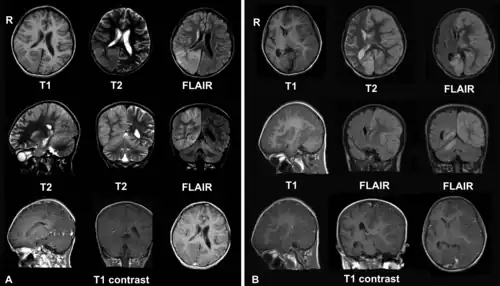

A. Diciembre de 2008, el paciente ingresa con cefalea y epilepsia partialis continua. Hay lesiones con inflamación local en los lóbulos parietal y occipital del hemisferio derecho del cerebro y del hemisferio derecho del cerebelo.

B. En abril de 2009, el mismo paciente, ahora en estado de coma con epilepsia partialis continua. Hay deterioro debido a la encefalitis - existe compromiso del hemisferio cerebral izquierdo con edema cerebral severo y desplazamiento de las estructuras de la línea media.